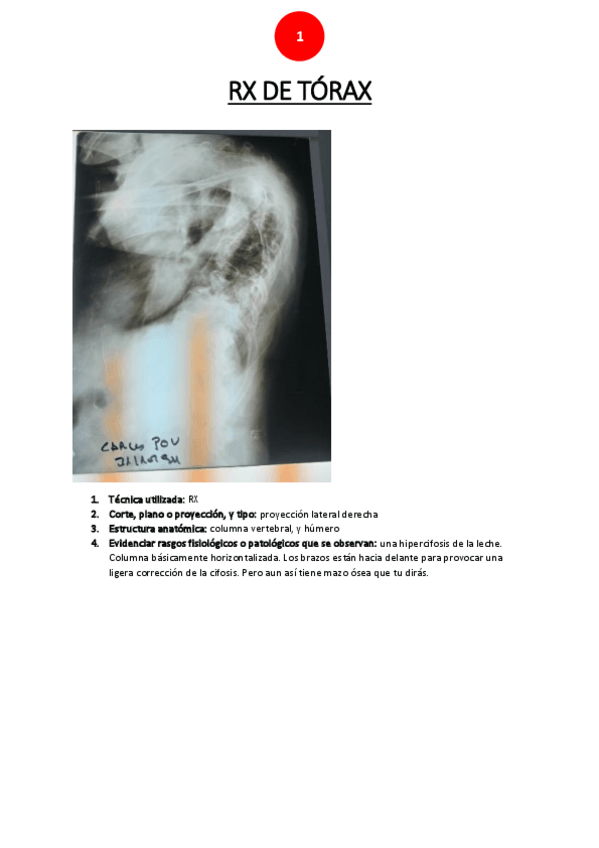

Prácticas - RX-torax.pdf

16 páginas